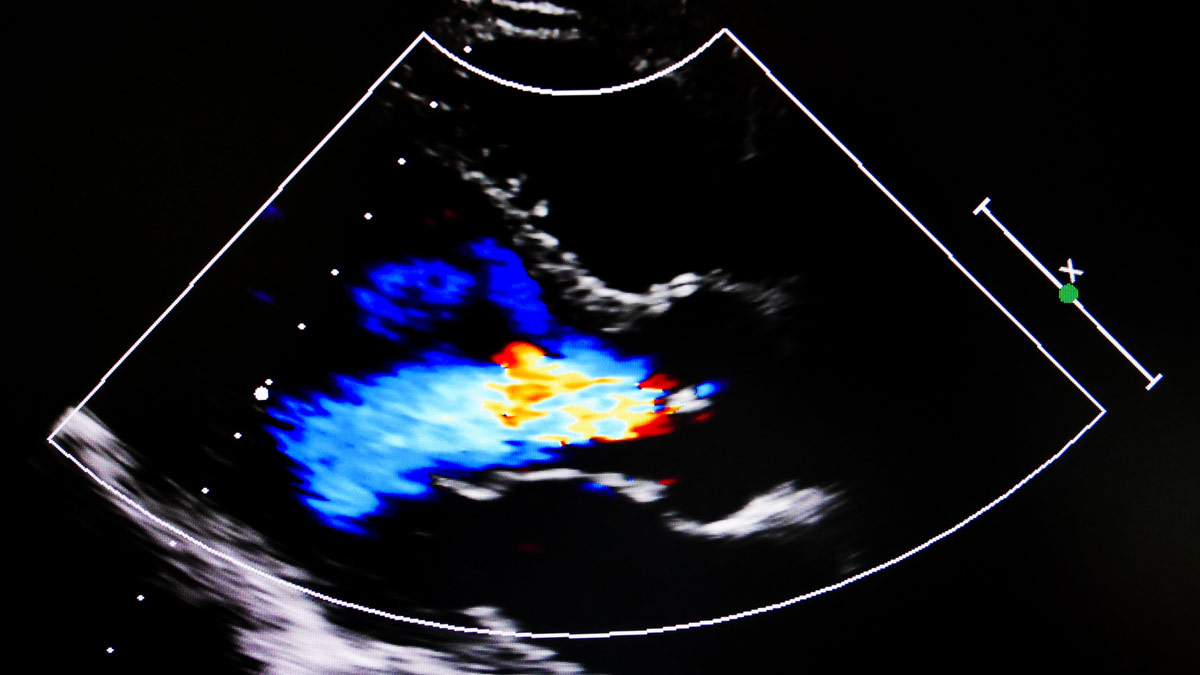

Echocardiography focuses on the evaluation of the heart, its valves and chambers, and associated vessels. The echocardiography certificate produces competent, compassionate, and responsible professionals and leaders who are skilled in ultrasound scanning techniques and the operation of ultrasound instrumentation.